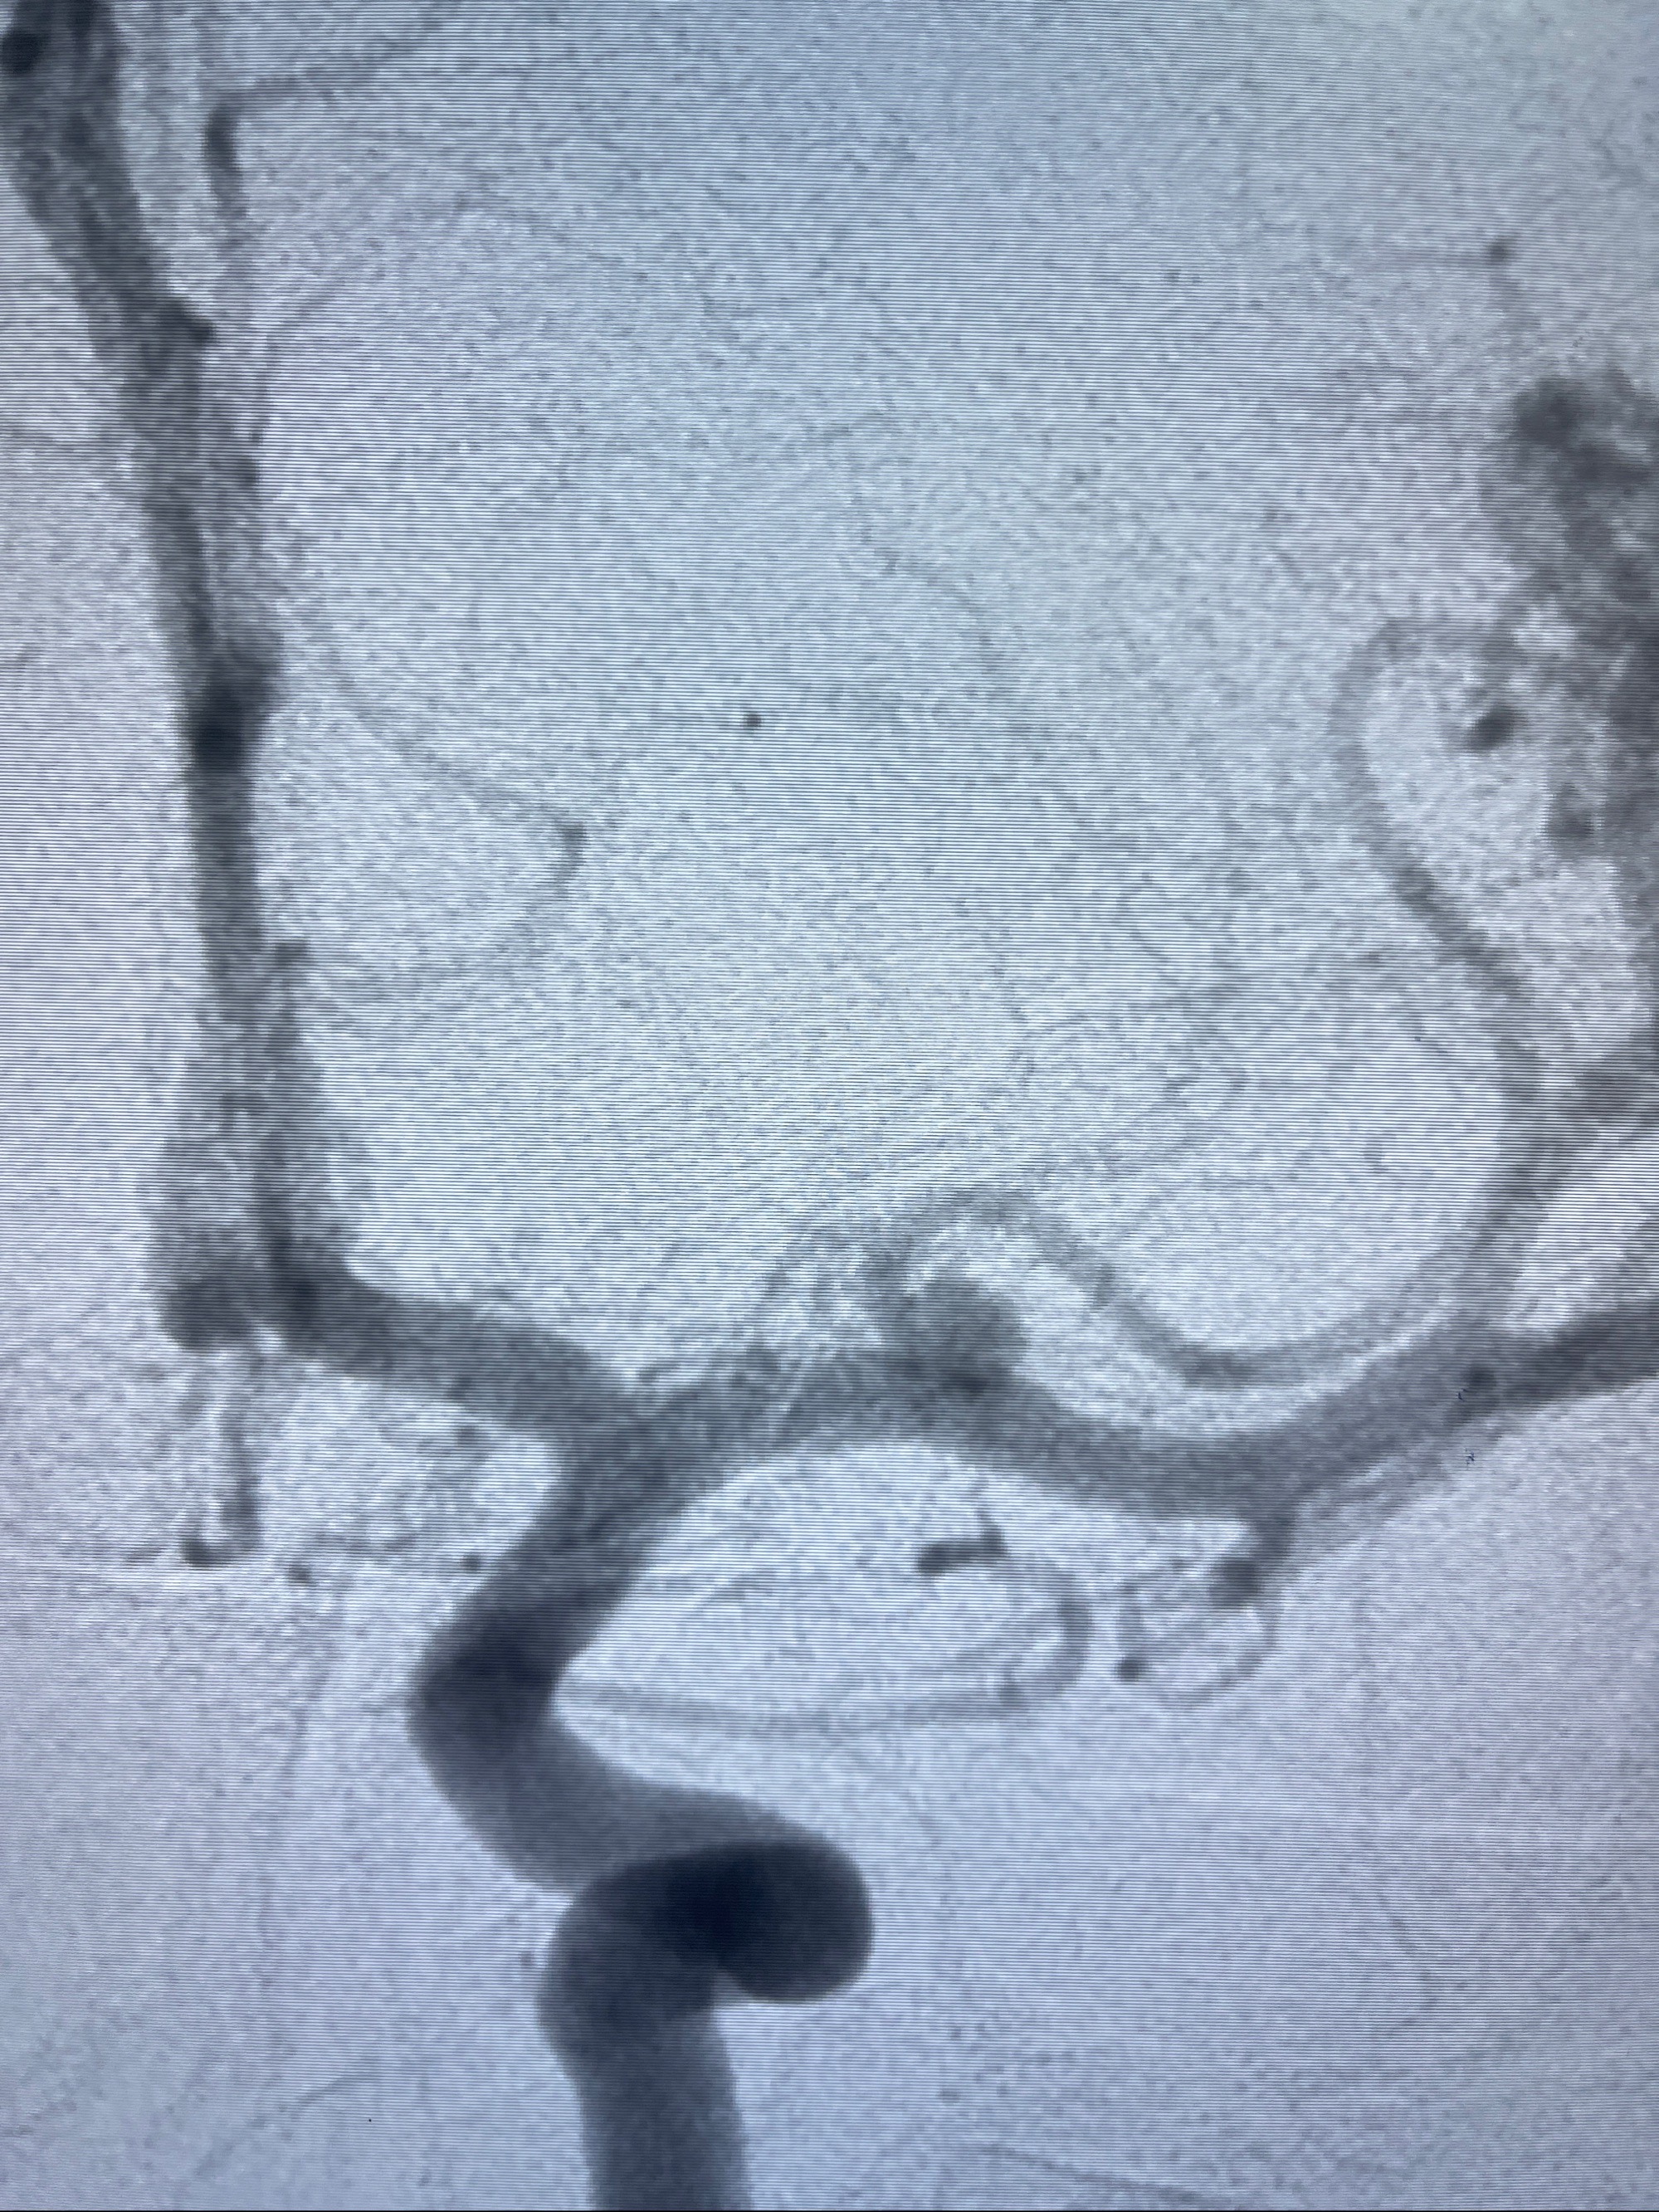

2023-08-14DSA:

左侧大脑中动脉动脉瘤,约2.6-2.8-3.4-2mm大小(瘤颈部、瘤体部、瘤高)

1.左侧大脑中动脉动脉瘤,约2.6-2.8-3.4-2mm大小(瘤颈部、瘤体部、瘤高)

2.外科手术夹闭or介入支架辅助栓塞